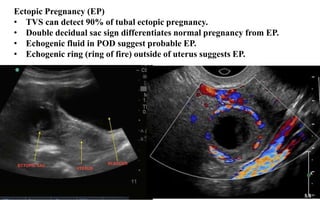

Ectopic Pregnancy (EP)

• TVS can detect 90% of tubal ectopic pregnancy.

• Double decidual sac sign differentiates normal pregnancy from EP.

• Echogenic fluid in POD suggest probable EP.

• Echogenic ring (ring of fire) outside of uterus suggests EP.